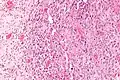

Histologically, epithelioid sarcoma forms nodules with central necrosis surrounded by bland, polygonal cells with eosinophilic cytoplasm and peripheral spindling.[3] Epithelioid sarcomas typically express vimentin, cytokeratins, epithelial membrane antigen, and CD34, whereas they are usually negative for S100, desmin, and FLI1 (FLI-1).[3] They characteristically lack the protein INI1 (see below). Epithelioid sarcomas typically stain positive for CA125.[4]

Intermed. mag. High mag.

High mag. High mag. (SMARCB1)